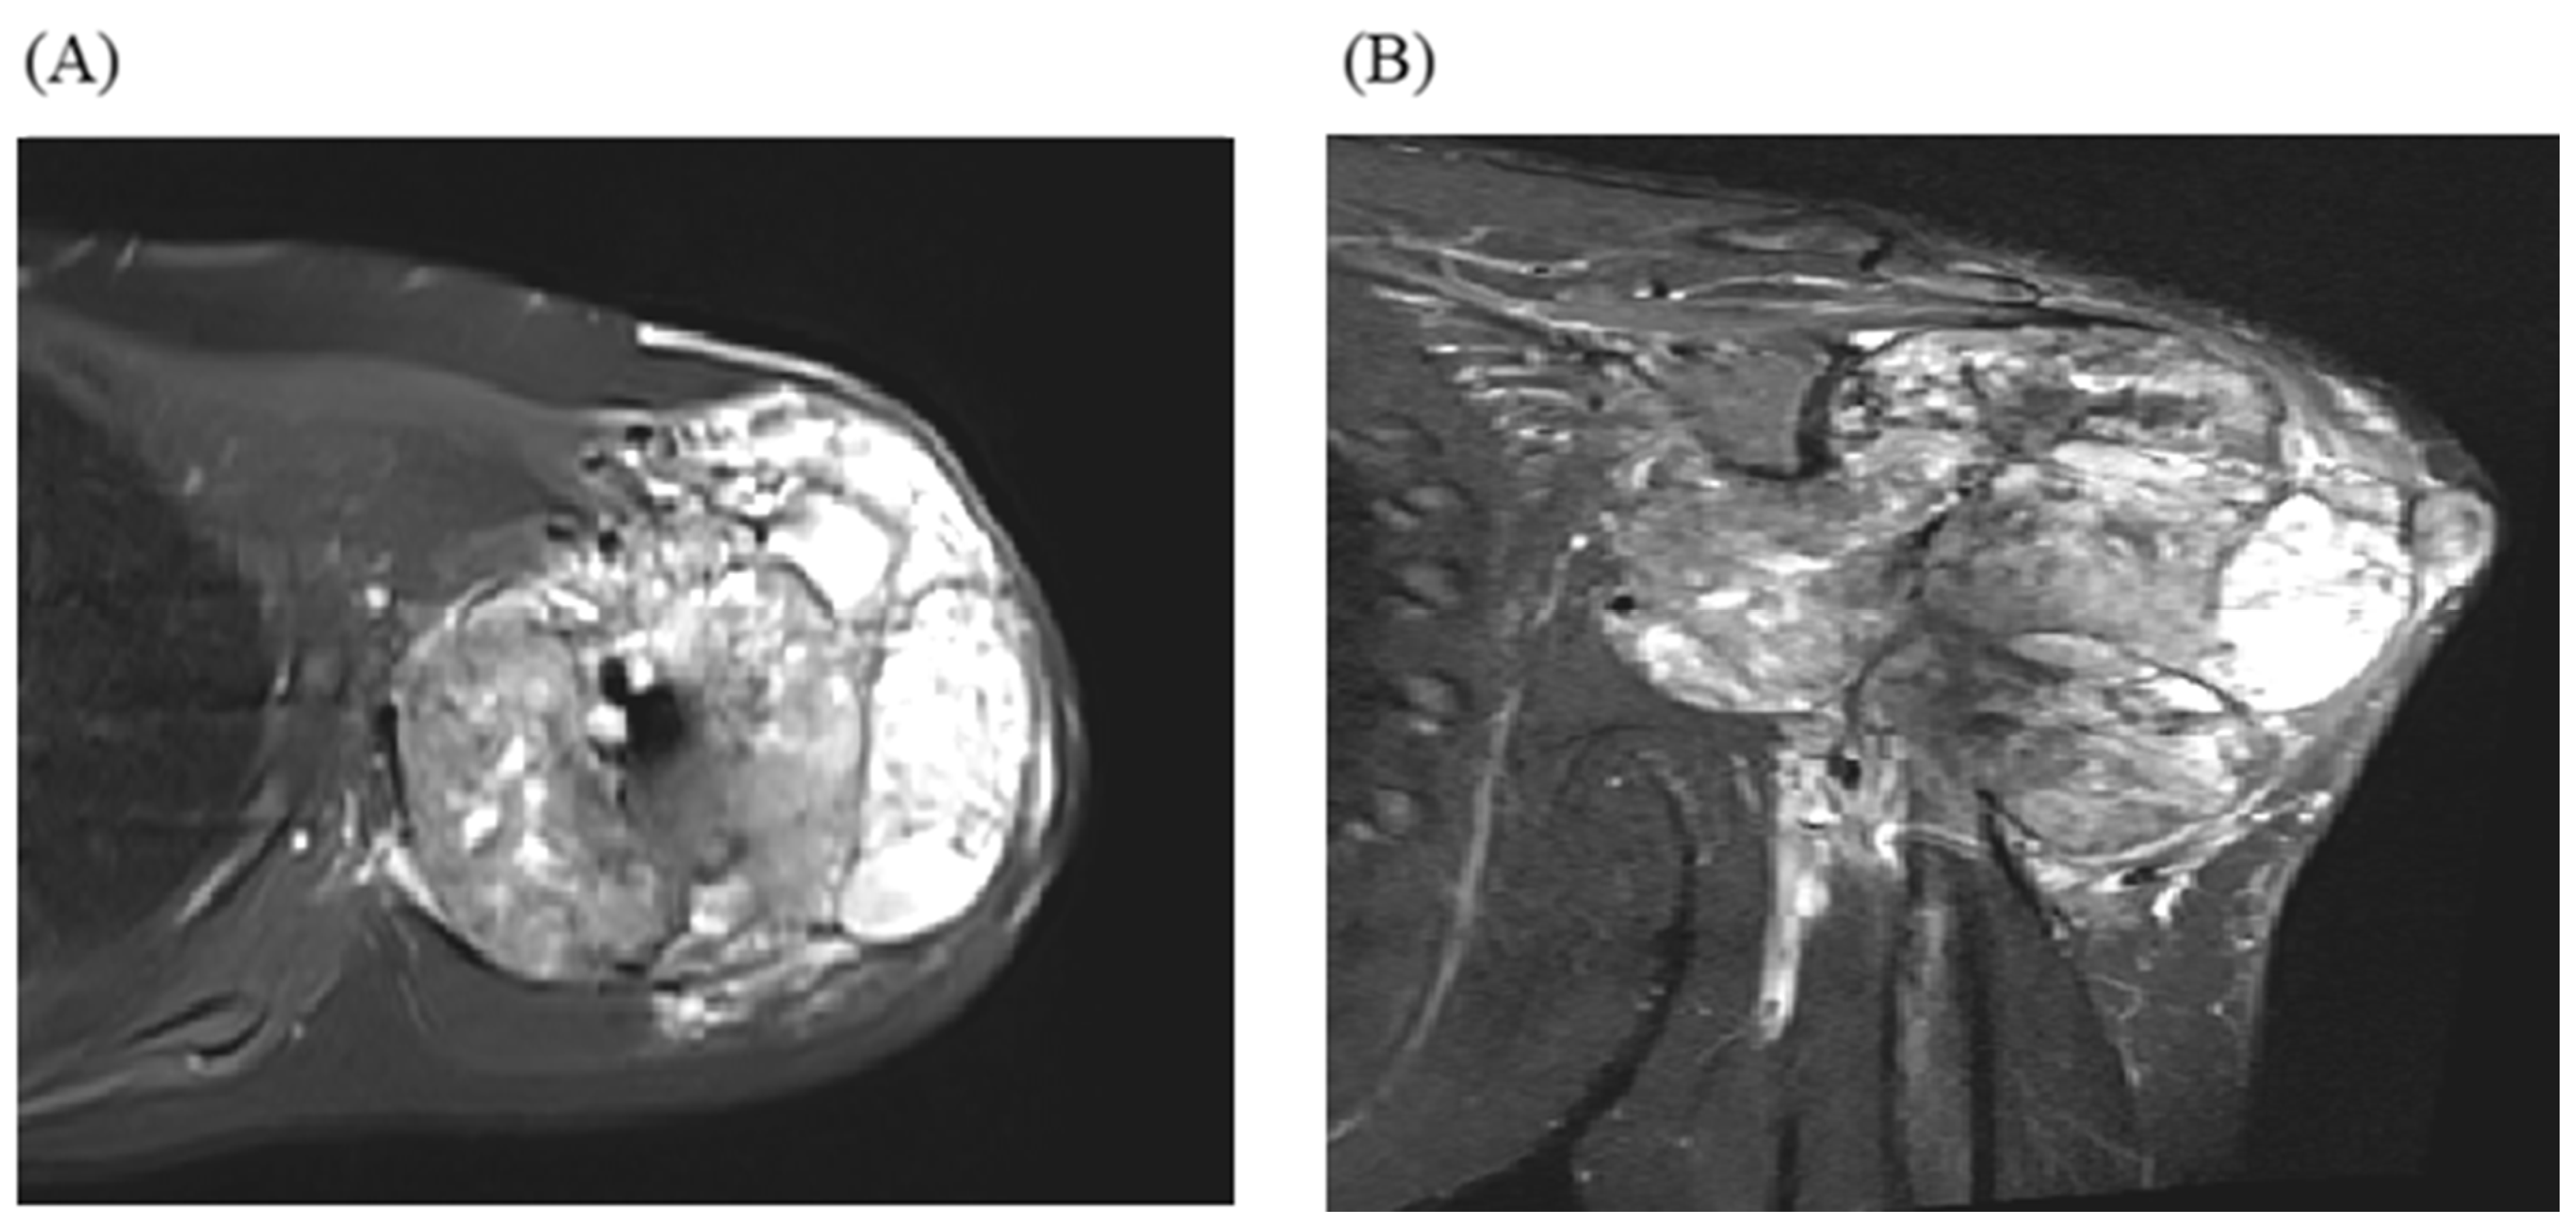

- Samargandi, R.; Bernard, M.; Miquelestorena-Standley, E.; Le Nail, L.R. Efficacy of denosumab treatment for lung metastasis secondary to proximal humerus chondroblastoma. Saudi Med. J. 2024, 45, 633. [Google Scholar] [CrossRef]

| Samargandi. [93] | 19/M | Proximal humerus | Lung, shoulder metastasis to lung | Late metastasis without local recurrence | Benign | 1 year 3 months | 2 years | Alive at last follow-up | Partial metastasectomy and denosumab |